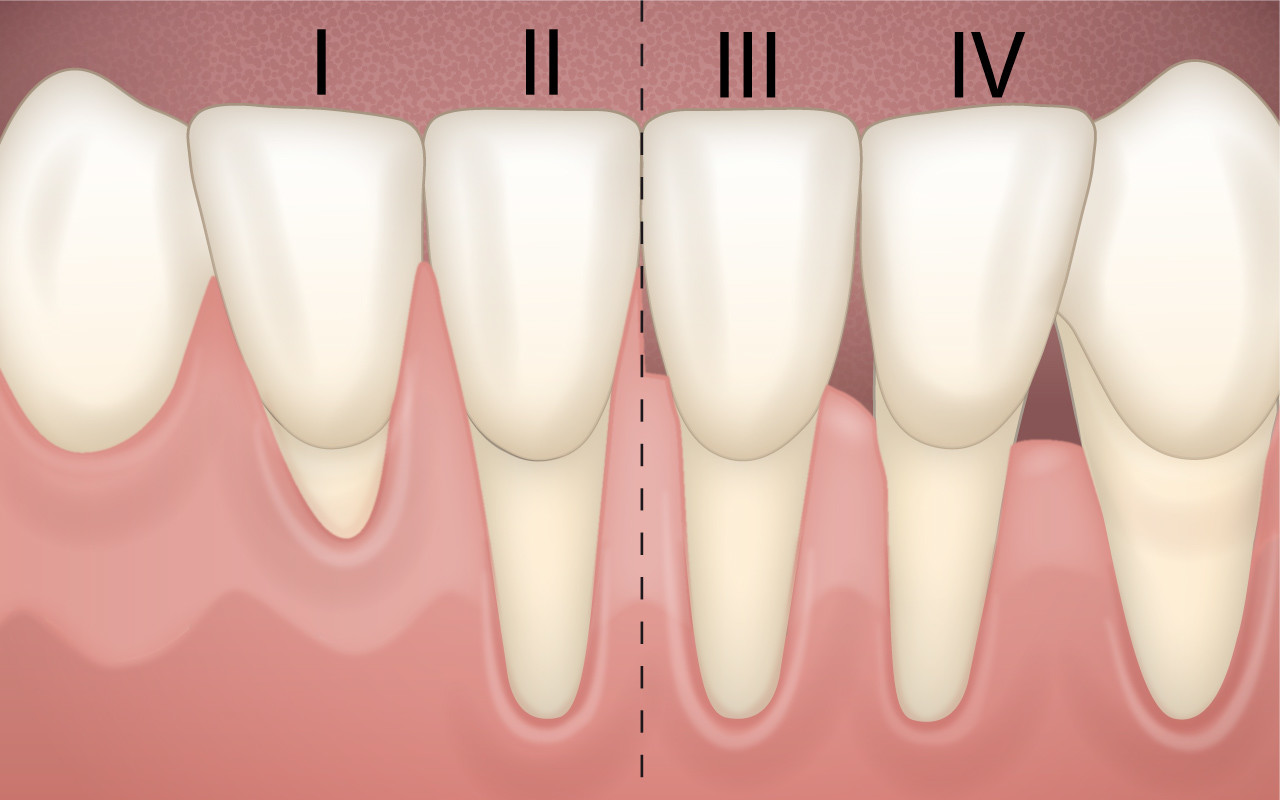

Schweregrad der Zahnfleischrezession

Zahnfleischrezessionen werden in unterschiedliche Schweregrade eingeteilt. Je nach Schweregrad stehen nur eine geringe Auswahl von Behandlungsmöglichkeiten zur Verfügung.

Bei Zahnfleischrezessionen werden vier Schweregrade voneinander unterschieden, weil sich daraus auch die Behandlungsmöglichkeiten herleiten lassen.

Eine einfache Rezession liegt vor, wenn die Rückbildung des Zahnfleischrandes noch nicht bis zur beweglichen Mundschleimhaut vorgedrungen ist. Beim zweiten Schweregrad ist die Rezession bereits in die bewegliche Schleimhaut vorgedrungen. In beiden Fällen ist die Korrektur des Zahnfleischrandes mit einem chirurgischen Eingriff möglich.

Da bei den Schweregraden 3 und 4 bereits auch Kieferknochen zwischen den Zähnen abgebaut worden ist, können dort vorhandene Zahnfleischrezessionen auch nicht mit chirurgischen Massnahmen vollständig korrigiert werden.